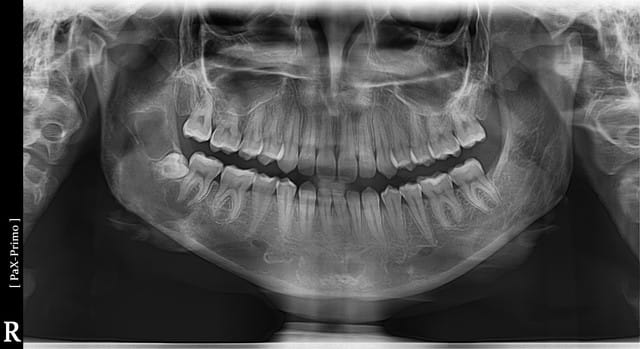

Bonsoir à tous, pourriez vous me dire si vous trouvez vous aussi suspecte cette image au niveau de la 48.

C'est si gros que j'ai un doute.

Sinon la réponse est oui, bien vu, tu as repéré une image suspecte correspondant à une vraie lésion. Reste à déterminer la nature de cette lésion. Difficile sur un otp mais on peut très fortement exclure un kyste dentigère étant donné l'aspect.

diagnostic probable: kyste osseux essential

diagnostic probable: kyste osseux essentiel (pseudokyste)

J'aime moins la zone radio translucide au niveu de la branche montante droite.

On a qd même la nette impression que çà attaque aussi la basale, il n'y a pas qu'une image derrière et devant la dds, çà occupe à mon avis la totalité de l'angle mandibulaire, avec plusieurs lobes de volumes différents => çà pue l'améloblastome. Le scan en dira plus. Met nous les principales coupes du scan sur le forum quand il sera fait stp.

+1 pour l'améloblastome,